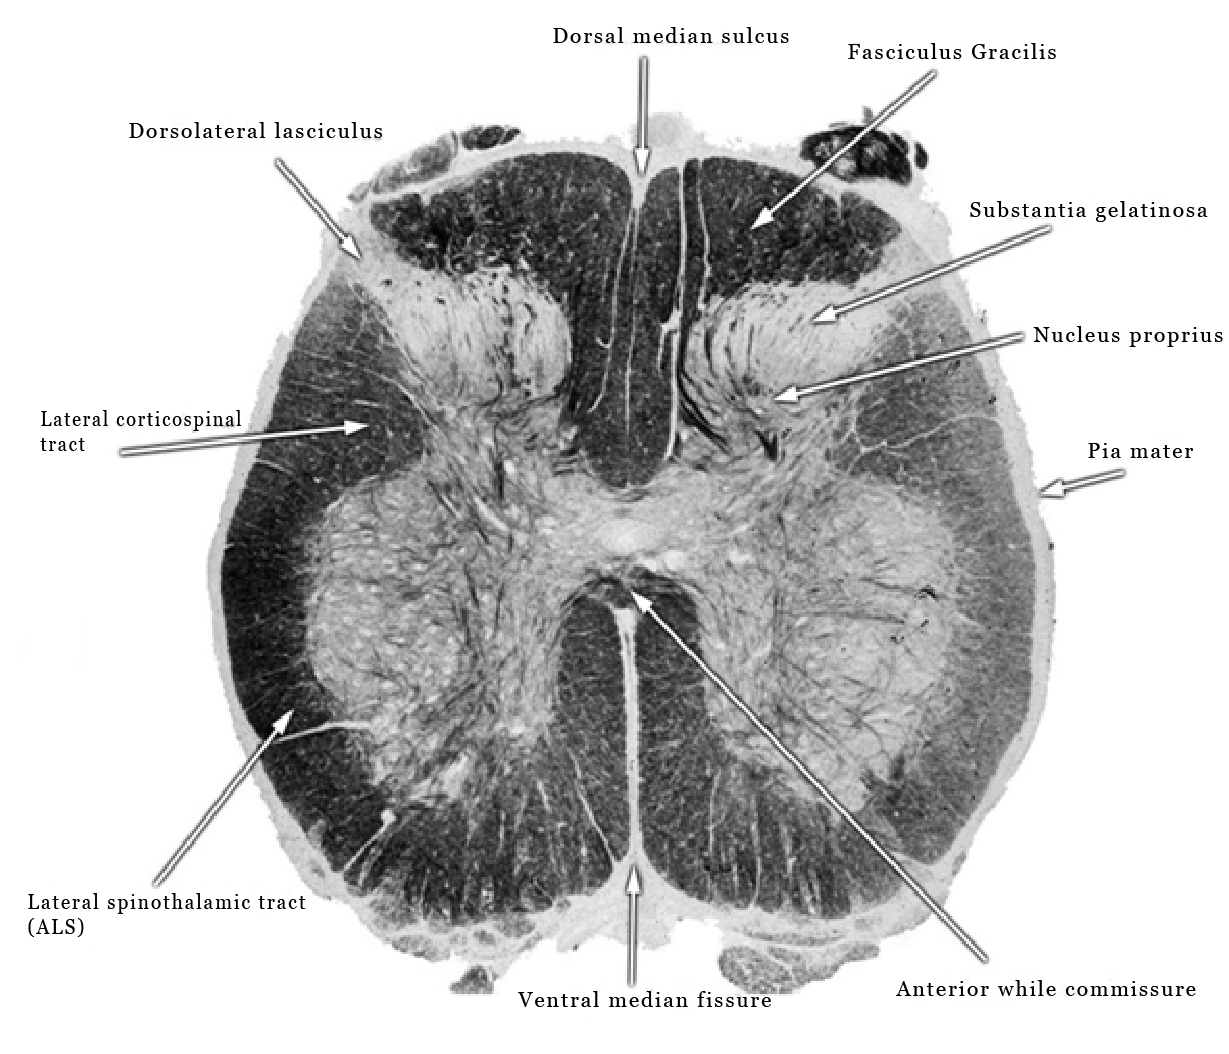

The meningeal tissue is the same from the surface of the brain to the tip of the spinal cord [5]. The dorsal median sulcus and the ventral median fissure of the spinal cord, (Figure 2), show a strong genetic influence having the same blueprint structure in all humans.

Figure 2: Cross section of human spinal cord, dorsal median sulcus, ventral median fissure.